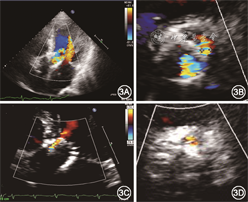

经心脏团队讨论后建议患者首选外科主动脉瓣置换术,术中探查主动脉根部,必要时考虑行带主动脉瓣人工血管升主动脉替换术(Bentall手术);次选方案可考虑再次行TAVR联合PVL介入封堵术。患者拒绝外科手术,要求介入治疗。2019年12月26日在全麻下行再次TAVR联合PVL介入封堵术。手术过程(图2):穿刺右侧股动脉置入7 Fr血管鞘,经鞘管送6 Fr猪尾导管至升主动脉窦底,主动脉造影提示重度人工瓣反流和PVL;将26 mm×4 cm NUMED球囊送至人工瓣膜假体内,快速起搏(180次/min),扩张球囊并行升主动脉造影,结果显示人工瓣无反流,瓣周反流显著,术前TTE显示人工瓣口重度反流信号,重度PVL;直头导丝(UniGlideTM,Cook Medical)经由JR 4造影导管穿过PVL隧道至左心室,交换0.036 mm×260 cm普通导丝至左心室,拟经普通导丝送5 Fr PDA/VSD输送鞘(北京华医圣杰科技有限公司)至左心室未能成功,交换超硬导丝(Amplatz Super StiffTM,Boston Scientific)至左心室,经超硬钢丝成功将输送鞘送至左心室;10~12 mm Plug Ⅰ型封堵器(北京华医圣杰科技有限公司)与推送钢缆连接,在PVL隧道左心室侧部分释放封堵器后回撤输送鞘至PVL隧道内,有阻力后封堵器近端于隧道主动脉侧完全释放;选择Vitaflow Ⅱ TAV27瓣膜支架(上海微创医疗器械公司),沿左心室钢丝送至瓣膜假体内,快速起搏(140 次/min)后“0”位释放。术后造影及TEE评估结果显示,无人工瓣反流,轻度瓣周反流。出院前复查TTE:人工瓣功能正常,轻度PVL(反流束宽度0.2 cm),中度二尖瓣反流,轻度三尖瓣反流,舒张期左心室内径6.0 cm,左心室射血分数45%。术前与术后TTE对比见图3。